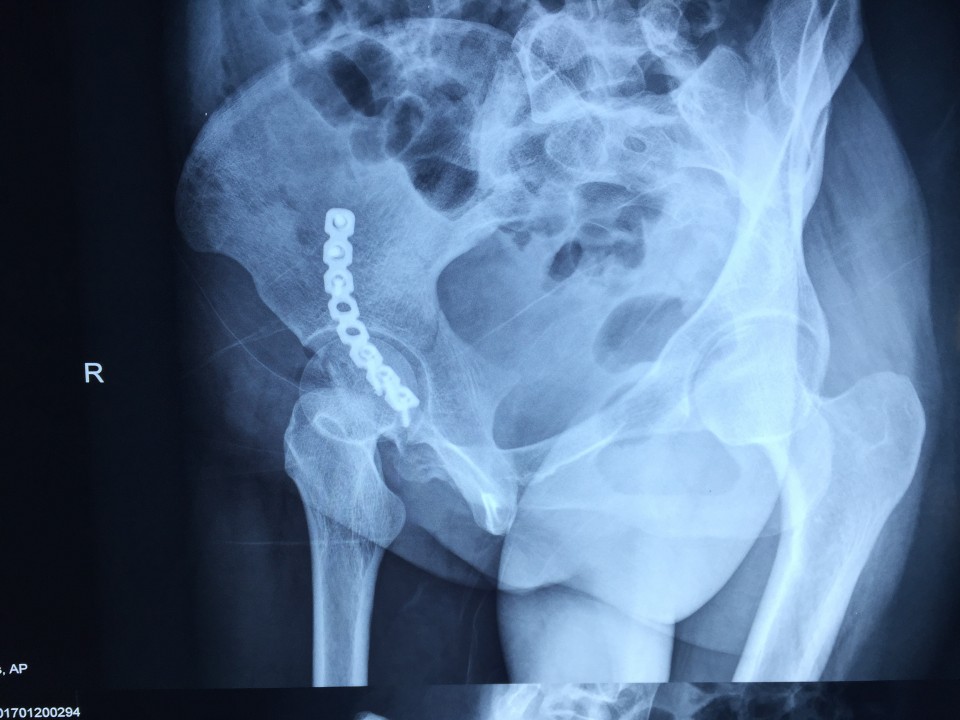

近日,我院创伤骨科七东利用改良Stoppa经腹白线旁入路成功治疗一例髋臼骨折患者。该患者女性,27岁,骨盆车祸伤。术前检查诊断为右侧髋臼骨折(AO分型为A3型)。该患者有剖宫产病史,腹部组织粘黏严重,手术难度较大。经过科室专家多次会诊,刘德宝主任制定详细手术方案,决定术中采用改良Stoppa入路,以减少手术创伤的影响。最终该手术顺利完成,历时一小时余,术中出血仅200ml,术后患者恢复良好。 采用改良Stoppa入路治疗髋臼骨折为安徽省首例,标志着我院创伤骨科进一步迈入创伤省内领先,国内先进的水平。

传统的对于髋臼前壁骨折的治疗方式主要为髂腹股沟入路,此入路内有重要的神经、血管经过,操作费时,术中可能导致股神经、血管及股外侧皮神经、精索或圆韧带的损伤。且骨折需通过3个窗口显露,骨折区域显露有限。针对髂腹股沟入路的缺点,我们使用改良Stoppa入路弥补了髂腹股沟入路的不足,它采用腹白线旁入路,推开腹膜内脏器,腹膜外达到真骨盆缘,一个窗口获得骨盆术野,可很好显露骨盆环。它有以下优点:此入路有宽阔的视野,并能直视骨盆缘,故可有效处理“死亡冠”,减少出血的发生;钢板塑形简单,钢板置入区域真骨盆内缘平坦,只需在一个平面预弯即可,并不需扭转钢板;可双侧骨盆缘复位固定,对于双侧耻骨上支及髋臼前柱骨折可轻易达到;术后病人康复快,因患者经下腹正中入路,并未损伤到髋部周围各层肌肉组织,故患侧肢体术后康复较快。据悉,此项技术在国内仅少数医院开展,在省内尚属首例。